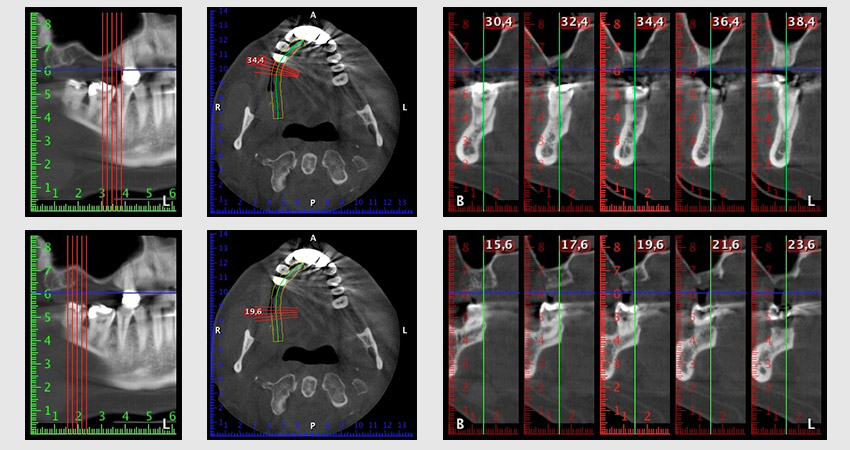

Шест месеца след екстракцията на зъби 16 и 14 се извършва преглед с дигитален томограф (DVT, Planmeca), с цел планиране и намаляване на възможните рискове. Ясно се вижда, че костта не се е регенерирала до желания обем (Фиг. 2 до 7).

Снимки 2 до 7: DVT със силно намален хоризонтален костен обем.

Синус лифтът е задължителен и за двете зони 16 и 14, за да се гарантира фиксирано възстановяване, базирано на поне два импланта. Сравнително голяма костна аугментация е необходима, тъй като обемът на остатъчната кост е изключително малък в този случай. Процедурите с голяма костна аугментация са инвазивни и се свързват с висока заболеваемост на пациентите, както и отнемат много време и са скъпи. По-трудно е да се предвидят резултатите от лечението и рискът от неуспех е увеличен. Пациентката е информирана за големия риск и е предложено алтернативно решение, което тя последователно отхвърля.

За да ограничим аугментацията до зона 14, след консултация с пациентката, е планирано поставяне на имплант в зона 16, наклонен по посока на челюстта (Фиг. 8).

Този метод изисква винтово фиксиране за финално възстановяване. Необходим е ангулиран абатмънт (например 35°) така, че винтът да бъде перпендикулярен на оклузалната равнина, която позволява мостът да бъде захванат оклузално.

Снимка 8: DVT с план за ъгъла на поставяне на имплант 16